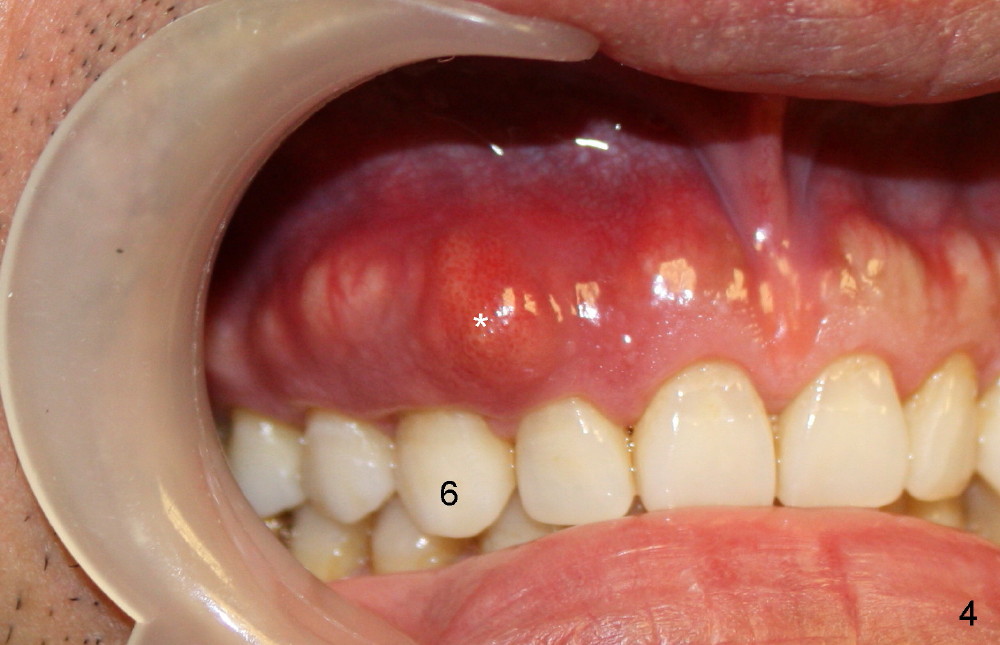

A male patient had trauma to the tooth #6 at the age of 13.  The affected tooth has remained asymptomatic for more than 30 years (Fig.1).   X-ray reveals an oblique root fracture (Fig.2 >) with radiolucency in the mesial alveolus (*, apparently normal trabecular pattern).  Six years later (Feb. 2011), an acute infection develops (Fig.4 *).  It requires incision & draining and antibiotic.  At that time, the trabecular pattern disappears around the fracture line mesially (Fig.3 *).  Four months later cone beam CT shows bone loss between #6 and 7 (Fig.5 *).  Root canal therapy is done as a palliative measure (Fig.6 R; C: Cavit).  Three months later, MTA (mineral trioxide aggregate) is placed in the coronal canal next to the fracture line (Fig.7 M).  It is hoped that MTA can promote nearby bone and cementum to regenerate to seal the fracture line.  Four months after MTA application, there is no sign of bone regeneration (Fig.8).  Bone is lost for approximately 7 mm.

The tooth is discolored probably due to the side-effect of MTA(Fig.9; photo taken 9 months post-MTA).  The mesial gingiva recedes (*).  There is mild persistent pain with purulent discharge mesiobuccally (Fig.10 >).  The corresponding pocket remains 7-8 mm deep in spite of root canal therapy and MTA.